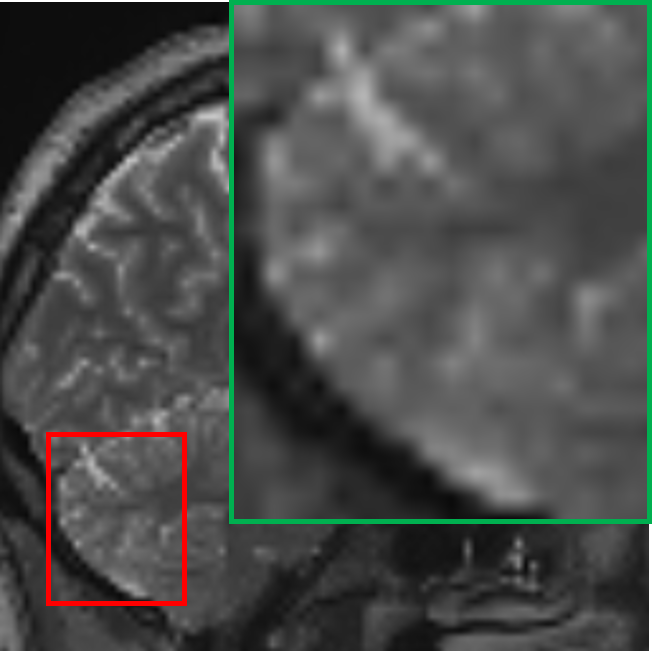

IV-D Deployable flexibility analysis of the student model

Beyond its lightweight architecture, the student model demonstrates a remarkable deployable ability to perform SR tasks across MRIs of varying resolutions without requiring additional training. This stems from its training process that involves exposing the student model to inputs and targets across a range of resolutions, equipping it with the ability to handle diverse resolution scales. For this, we explore two common SR scenarios: 1.5T to 3T and 3T to 7T MRI. We include the recently proposed Implicit Diffusion Model (IDM) [35], a novel method for continuous image SR, as a benchmark in our evaluation. In our study, the voxel sizes of the MRI scans are 2mm×\times×2mm×\times×2mm for 1.5T, 1.5mm×\times×1.5mm×\times×1.5mm for 3T, and 0.7mm×\times×0.7mm×\times×0.7mm for 7T. Since the focus is on 2D slice-based SR, we configure both the magnification factors for IDM and the step allocations for our proposed student model to match the required SR ratios. Specifically, for the 1.5T to 3T scenario, a magnification factor of 1.8 is employed for IDM, corresponding to an allocation of 4 steps out of the total 20 steps for the student model. Similarly, for the 3T to 7T scenario, a magnification factor of 4.6 is applied for IDM, corresponding to an allocation of the remaining 16 steps for the student model.

As illustrated in Figure V, for the 1.5T-to-3T task, the teacher model is not applicable as it is designed to directly perform SR from 1.5T to 7T. The output of IDM in this scenario shows significant blurring, particularly in the cerebellum region, with minimal perceptible improvement over the input, indicating a limitation in capturing the finer structures. In contrast, our student model achieves results that closely resemble the 3T ground truth, effectively recovering structural details and textures. For the 3T-to-7T task, the teacher model, when directly applied to 3T data, generates overly sharpened outputs, reflecting its sensitivity to input-specific constraints and its lack of adaptability to intermediate resolutions. However, the student model consistently outperforms IDM in this scenario as well, delivering results with better alignment to the 7T ground truth and more balanced enhancement of fine details. These observations highlight the flexibility and robustness of the student model across varying resolution scales, emphasizing its superiority in deployable SR scenarios.